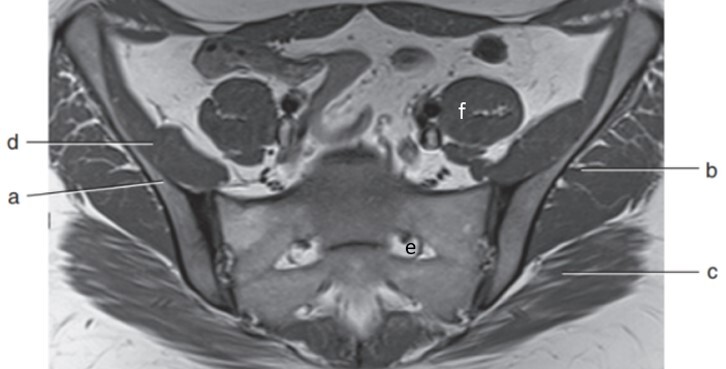

2

Q

Label a-f

A

a. Ala (Rt Ilium)

b. Lt gluteus medius

c. Lt gluteus maximus

d. Rt iliacus

e. Lt sacral foramen

f. Lt psoas